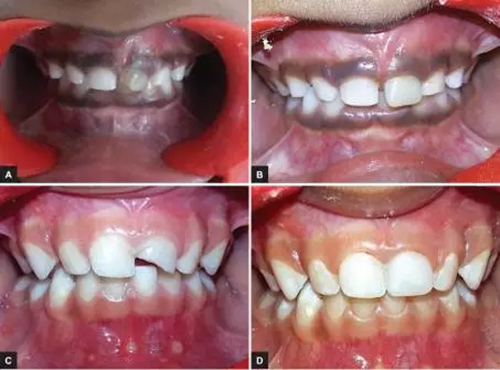

本研究中,其他患齲齒或牙外傷的患兒均采用此方法使用臨時冠材料進行美學(xué)修復(fù),下圖分別為兩例乳前牙齲齒(圖2)和兩例牙外傷(圖3)的病例。

圖3.(3-A,3-B為乳前牙外傷病例1 3-C,3-D為乳前牙外傷病例2)